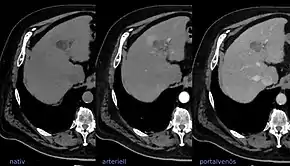

![]() LIRADS classification is applied to multi-phase contrast-enhanced CT or MRI scans in people with certain chronic liver diseases. | |

The Liver Imaging Reporting and Data System (aka LI-RADS) is a quality assurance tool created and trademarked by the American College of Radiology in 2011 to standardize the reporting and data collection of CT and MR imaging patients at risk for hepatocellular carcinoma (HCC), or primary cancer of the liver cells.[1] It provides a standardized framework for classification of liver lesions by a radiologist, and only applies in patients with chronic liver disease, the main risk factor for liver cancer. The hierarchical classification, from LR1 to LR5, is based on specific imaging features of the lesion in question, and corresponds to the degree of suspicion for malignancy. For example, a lesion with features corresponding to the highest category, LR5, is "definitely" HCC. Importantly, the increasing acceptance of the LI-RADS system of reporting by referring clinicians (chiefly oncologists, hepatobiliary and liver transplant surgeons) has reduced the need for tissue biopsy confirmation of cancer in patients with chronic liver disease.